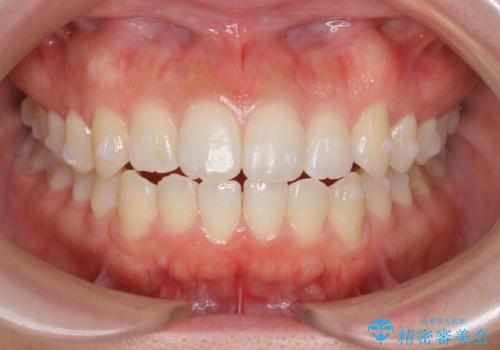

前歯のすれ違い インビザラインで行うマウスピース矯正

- 前歯のガタつき、でこぼこ、前後が逆になっている噛み合わせの改善を求めて来院されました。

治療の装置が目立たず歯ブラシのしやすいマウスピース矯正インビザラインでの治療を計画します。

20時間/日の装用時間をしっかりと守っていただき、きれいな歯並びを手に入れることができました。